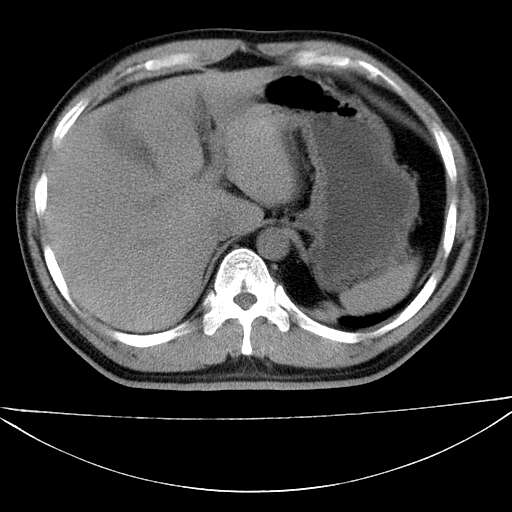

标题: CT21921:腹膜后腔肿物。患者男39Y。体检。增强扫描时间欠准

左侧膈肌脚外缘见一结节样软组织影,密度较均匀,与胸膜关系稍密切,增强轻度强化;考虑来自胸膜良性病变(胸膜纤维瘤可能)。建议加扫胸部ct检查。

2、左下膈肌脚外缘结节状病变,与胸膜交界面呈锐角,胸膜下脂肪线可见,定位于肺内,考虑支气管囊肿或肺隔离征可能性大。

1)考虑左肺下叶后基底段(或左下胸后壁胸膜)软组织团块,性质待定;建议行进一步检查。2)左肾结石。

左膈肌连续性中断,左侧膈疝可能性大.

左膈肌角后腹膜腔见肿物影,其内见脂肪密度灶及软组织密度灶,强化不明显。病灶大部在后腹膜内。考虑异位嗜铬细胞瘤或脂肪肉瘤、畸胎瘤

左膈肌连续性中断,左侧膈疝可能性大

左下肺隔离症,可见从胸主动脉发出异常血管供应